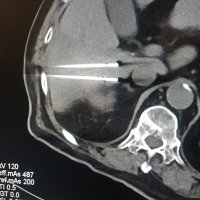

Tumor

• Luka Novosel i tim

• tumor

• operacija

KBC Sestre milosrdnice Izvor: Promo fotografije / Autor: KBC Sestre milosrdnice